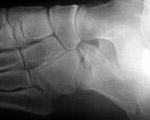

What abnormality is shown here?